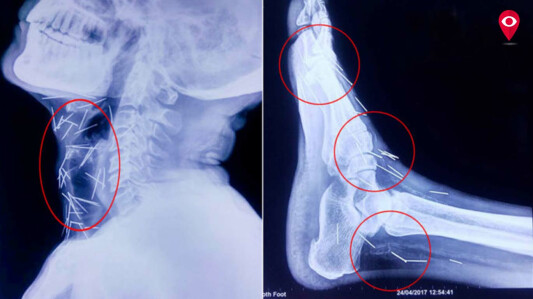

राजस्थानच्या बुंदी तालुक्यातील महिपुरा बस्ती येथे राहणाऱ्या बद्रीलाल यांच्या शरीरात जवळपास 75 पेक्षा जास्त टाचण्या असल्याचं समोर आलं आहे. 56 वर्षीय बद्रीलाल आठवड्यापूर्वी मुंबईच्या जगजीवन राम हॉस्पिटलमध्ये दाखल झाले आहेत. त्यांच्यावर उपचार करणाऱ्या डॉक्टरांचं म्हणणं आहे की, या टाचण्या फक्त शस्त्रक्रियेद्वारेच काढता येऊ शकतील. बद्रीलाल यांच्या घशाच्या भागात अंदाजे 40 पीन्स आहेत. तसंच, हात आणि पायांमध्येही टाचण्या आढळून आल्या आहेत. ही एक असाधारण केस असल्याचं डॉक्टरांचं म्हणणं आहे.

बद्रीलाल पश्चिम मार्गावरील ट्रेनसाठी पाणी सोडण्याचं काम करतात. एक्स-रेच्या अहवालानुसार, त्यांच्या शरीरात 75 टाचण्या आढळून आल्या आहेत. ज्यामुळे त्यांना 'टाचण्या खाणारी व्यक्ती’ असं नाव देण्यात आलं आहे. बद्रीलाल यांना राजस्थानमधील कोटा इथल्या एका रुग्णालयातून मुंबईतल्या रुग्णालयात पाठविण्यात आले. त्यांच्या शरीरात सुमारे 75 टाचण्या आहेत. मान आणि वरच्या छातीमध्ये 40 टाचण्या आहेत. त्यांच्या उजव्या पायात 25 आणि उजव्या आणि डाव्या हातात 2-2 टाचण्या आढळून आल्या आहेत.

बद्रीलालला काहीच आठवत नाही. त्यामुळे नेमकं कारण कळू शकलेलं नाही. याविषयी तज्ज्ञांशी बोलून पुढे काय उपचार द्यायचे ते ठरवणार आहोत. आम्ही बद्रीलाल यांना खूप प्रश्न विचारले पण त्यांनी काहीच उत्तरं दिली नाही. मग, आम्ही त्यांची चौकशी करून त्यांच्या काही टेस्ट केल्या. त्यानंतर त्यांच्या शरीरात असणाऱ्या टाचण्या दिसून आल्या. घशात दिसलेल्या टाचण्या काढण्यासाठी मोठी मेहनत घ्यावी लागेल. बद्रीलाल यांच्या अनेक तपासण्या करण्यात आल्या. त्यांच्या गळ्याचा एक्स-रे ज्यावेळेस काढला तेव्हा अनेक टाचण्या त्यांच्या घशात आढळून आल्या. त्यानंतर त्यांच्या घशाचा, छातीचा, दोन्ही हातांचा, दोन्ही पायांचा एक्स-रे काढला गेला. त्या एक्स-रे मध्ये भरपूर टाचण्या आढळून आल्या. त्यांच्या शरीरात असलेल्या टाचण्या शस्त्रक्रियेद्वारेच काढता येतील. त्यासाठी इएनटी आणि छातीच्या विशेष तज्ञ्जांची मदत घेतली जाईल. बद्रीलाल यांच्या शरीरातून या टाचण्या काढणं हे आव्हान आहे.